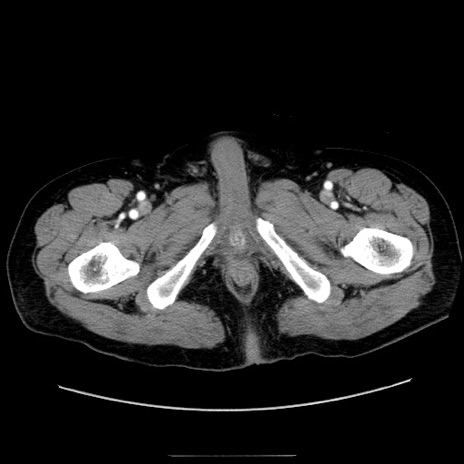

症例30(横断像)

【症例】80歳代男性

【主訴】臍周囲痛

【現病歴】約6時間前から臍下部痛が出現。次第に腹部膨隆・背部痛も生じてきたため来院。背部痛の場所は変化しない。

【身体所見】意識清明、BT 36.3℃、BP  131/87mmHg、P 87bpm、SpO2 100%(RA)、臍周囲自発痛・圧痛あり、反跳痛なし、自発痛部位に一致して板状硬あり、腹部膨隆、腸雑音減弱、CVA tenderness両側陰性。